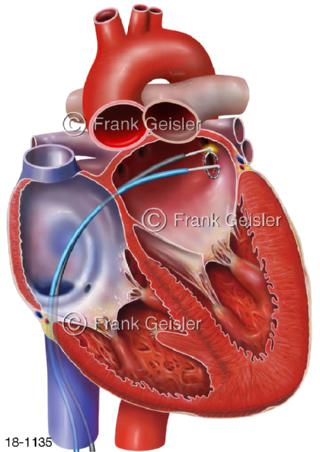

18-1135 Vorhofflimmern Herz, Katheterablation